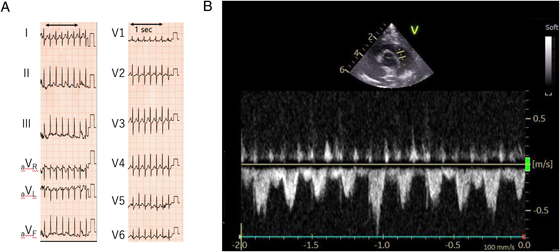

Current medical history: At 4 months of age, the patient re-visited his initial physician for a routine VSD checkup. During echocardiography to evaluate the VSD, his HR accelerated markedly with crying. The HR elevation appeared not to be attributed solely to sinus tachycardia associated with crying. As a precise measurement was challenging, the waveform of blood flow velocity across the main pulmonary artery was assessed using the pulse-wave Doppler method. The circumstance was confirmed with 12-lead ECG (Fig. 1A, B). His HR exceeded 300 beats/minute, prompting transfer to our hospital for further evaluation of the tachyarrhythmia.

Fig. 1 ECG and echocardiogram during tachycardia

(A) 12 lead-ECG at a previous hospital. HR 326 beats/min, constant RR interval, narrow QRS tachycardia. (B) Pulse-wave Doppler at a previous hospital Tachycardia with a V max interval <0.2 seconds (=heart rate >300 beats/min).